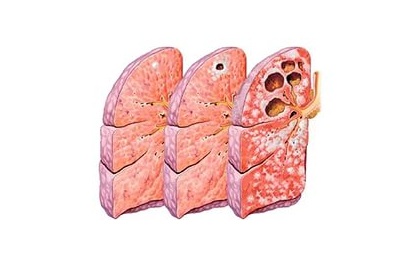

Классический вариант развития заболевания у взрослых и детей — легочная форма, характеризующаяся скоплением микобактерий (МБТ) с образованием туберкулем. Данные изменения регистрируются при помощи рентгена.

Часто интоксикационный синдром завершается выздоровлением, пораженные участки превращаются в соединительную ткань, воспаление стихает, а казеоз (измененная структура тканей) нейтрализуется солями кальция. Микобактерии трансформируются в неактивную форму, которая поддерживает противотуберкулезный иммунитет, но, с другой стороны, может стать причиной его реактивации при сильном снижении общего иммунитета.

Если лечение не проводится, интоксикация может стать хронической. При прогрессировании заболевания микобактерии поражают лимфатическую систему, попадая во внутригрудные отделы. Далее туберкулез переходит и в другие лимфоузлы, их поражает частичный или тотальный казеоз, который охватывает окружающие клетки, сосуды и бронхи.

Такая форма получила название туберкулеза внутригрудных лимфатических узлов, она наиболее распространена среди зарегистрированных форм первичного туберкулеза.

Вследствие естественного тока лимфы болезнь редко распространяется за пределы бронхов и не затрагивает легкие. По мере прогрессирования воспаления лимфоидная ткань превращается в грануляции и, увеличиваясь, способна распространиться почти на весь лимфоузел. Локальное поражение может быть значительным.

Воспаление проходит, казеоз кальцинируется, лимфоузлы принимают нормальное состояние. Излечение длительное, составляет 2-3 года. Осложнение данной формы заболевания – поражение ткани легких.

Первичный туберкулезный комплекс – наиболее тяжелая форма первичного туберкулеза, которая может затрагивать легкие, кишечник и другие органы. Развивается она при серьезных нарушениях в работе иммунной системы.

- в легких образуется очаг воспаления (первичный аффект),

- первичный аффект легочной ткани,

Первичный аффект может иметь различные размеры и даже охватывать целую долю легкого. Участок воспаления может развиться в любых сегментах легочной ткани.